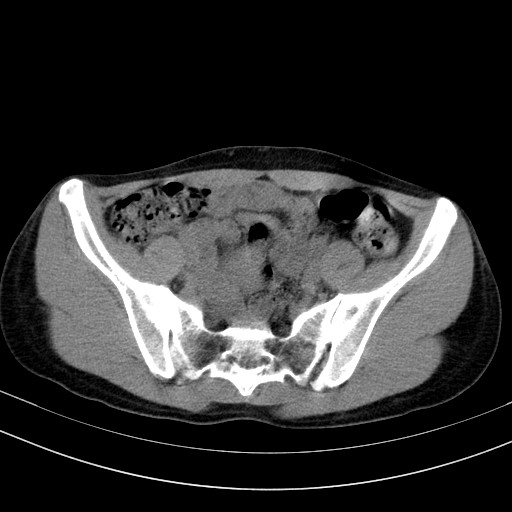

以下是引用随光逐影在2009-4-7 8:17:00的发言:[br]考虑宫颈占位性病变(宫颈癌?);建议行进一步检查。

以下是引用jiangjing在2009-4-7 16:46:00的发言:[br]宫颈增大,结构不清,右侧附件区可疑囊样占位,建议增强及mri 检查